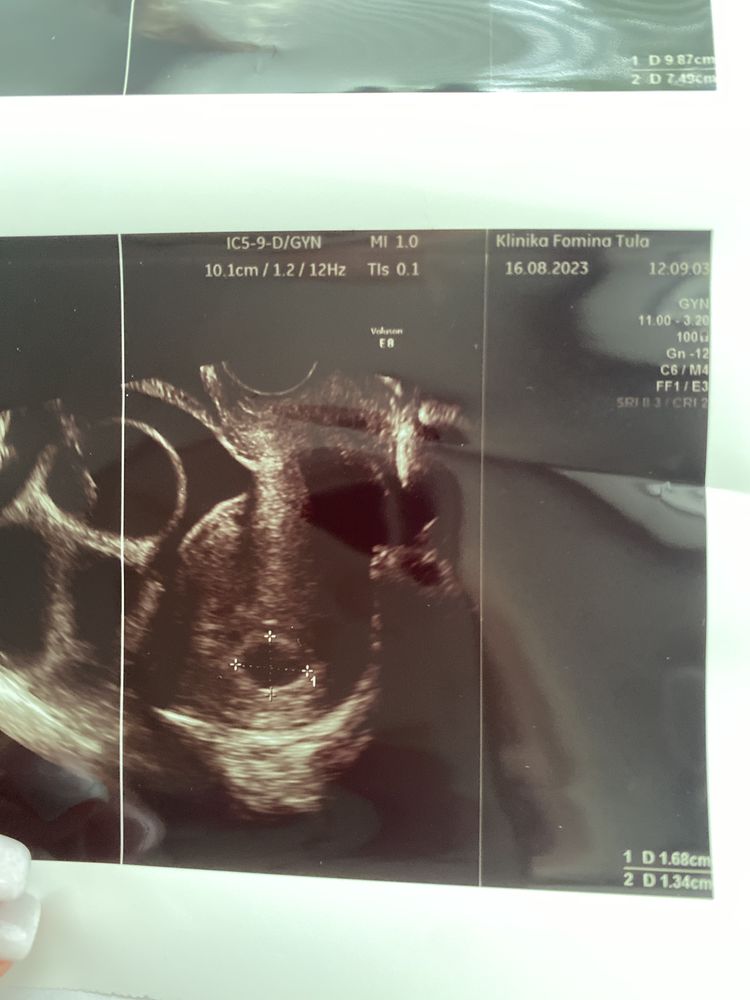

Но! 16 августа это 26 день после переноса, и там нету ничего кроме плодного яйца, я начала переживать, потому что девочки у которых вместе со мной в один день был перенос или на неделю позже уже есть желточный мешок…

Вот что у меня на узи том было 16 числа, просто дырка

это норм или я загоняюсь?

А я в левом верхнем углу вижу что то похожее на появление жм. Можете через 4дня переделать, уже точно должно всё быть) Может ещё УЗИ апарат такой, не увидели просто.